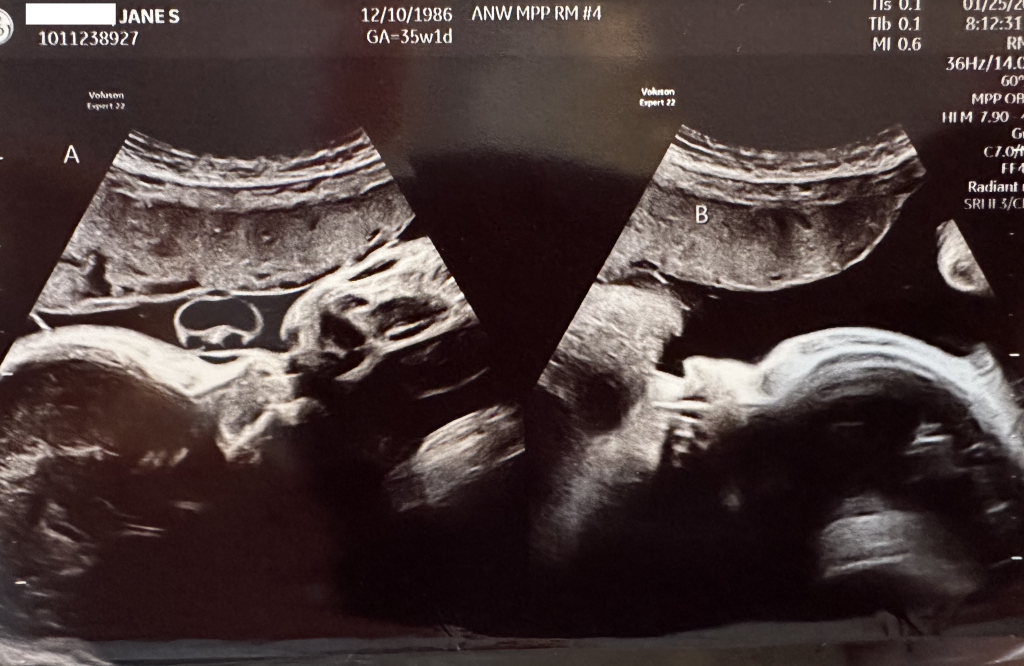

The entire team at Children’s has been more than amazing to work with and we just had our weekly checkup with them today. We are at 35 weeks and 1 day today, Luna is weighing in at 5lbs 6oz and Leo is at 6lbs 0oz, both doing great and on track for growth! Luna is still breech, but today Leo was cephalic… Jane has mentioned they both have been very very active at night, so there is still a chance Luna could flip around yet. Just in case, they had us schedule our C-section today which would take place on Feb 15th in the event they don’t come earlier.